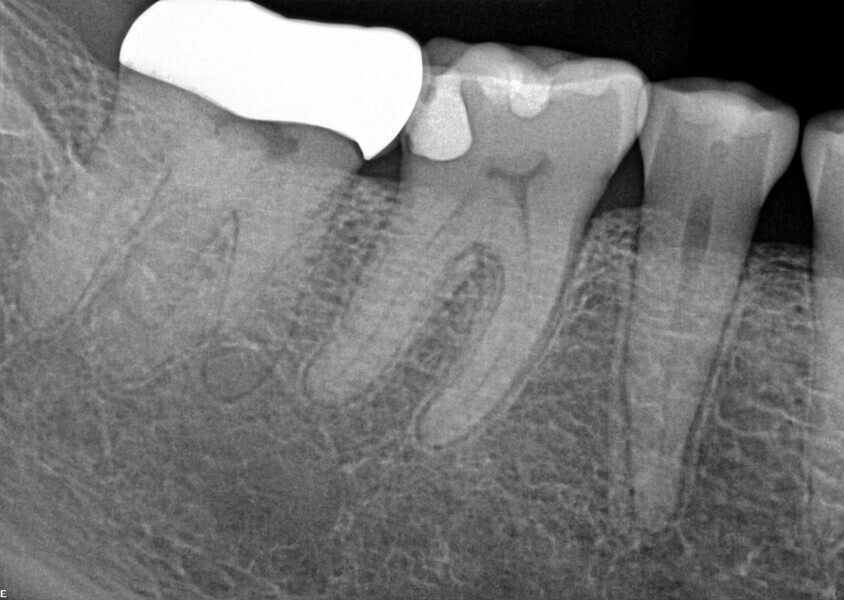

Fig. 14a: Case treated with Bassi Logic controlled memory nickel titanium files. Note the visualization of the third root on this lower molar and conservative canal preparation shape. (Courtesy of Dr. Alex Chan)

Fig. 14b: Case treated with Bassi Logic controlled memory nickel titanium files. Note the visualization of the third root on this lower molar and conservative canal preparation shape. (Courtesy of Dr. Alex Chan)